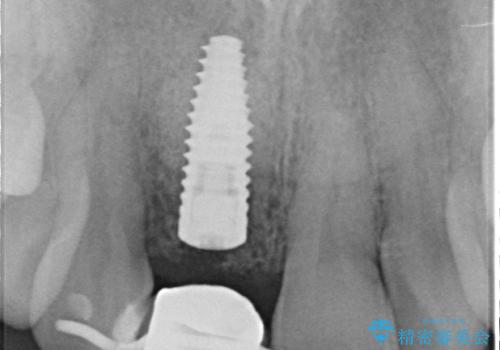

- 前歯を外傷により失い、審美性の改善を求めて来院されました。

横の歯を削る必要のあるブリッジ治療、着脱の必要な入れ歯に強い抵抗があったためインプラント治療を計画します。

審美的・機能的に良好な位置に埋入するには、骨量が十分ではなかったため骨の造成を併用したインプラント埋入外科手術を行います。

前歯のインプラントを審美的に仕上げるには、インプラント周囲に十分な骨の量と厚みのある歯肉、そして埋入位置の精密な位置付けが重要です。